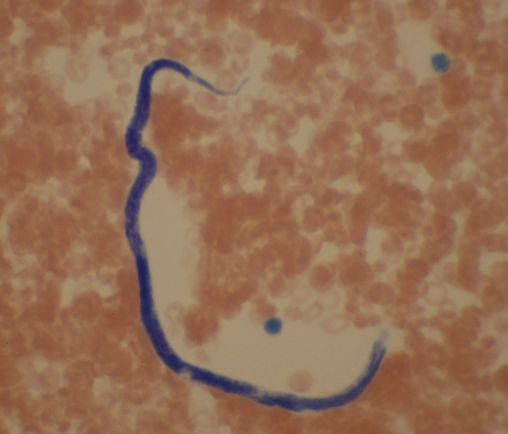

Dracunculus medinensis